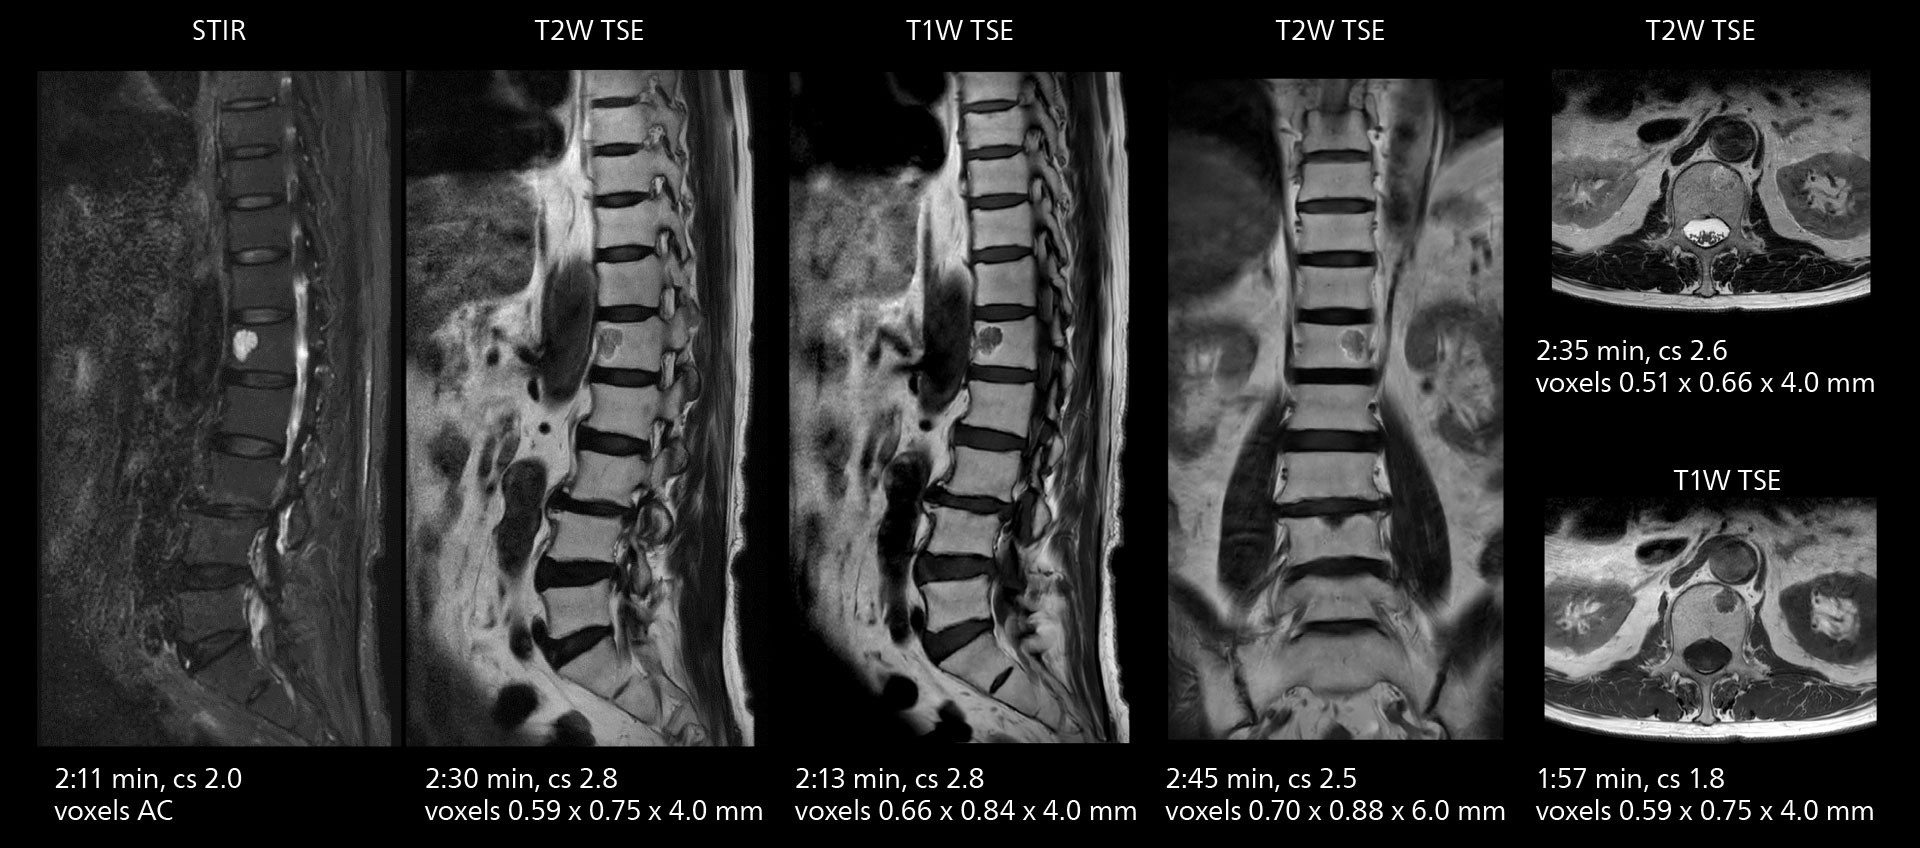

Sannodai Hospital radiologists had been very satisfied with their Ingenia 3.0T with Compressed SENSE, however after acquiring SmartPath to Elition X they have demonstrated improved image quality and even higher speeds in imaging studies throughout the body, according to Dr. Makuuchi. “Generally, we were impressed by seeing that images are very sharp and have higher SNR than we used to get with our Ingenia 3.0T system,” he notes. “We were delighted to see that high image quality can be obtained in a short time thanks to the Elition with its powerful An example of increased imaging speed is in knee studies. “There is a definite scan time reduction for T2* mFFE and proton density TSE – both of these sequences benefit from much shorter repetition times,” he reports.

gradients. Some high resolution examinations that were not possible before dueto their longer scan time, are now routinely performed with the upgraded system.”

Overall, imaging time per sequence has been reduced since the Elition X upgrade. This can help reduce the risk of patient movement and the need for rescans. “As our hospital has many elderly patients, we consider it important to obtain high-quality data in a short time,” Dr. Makuuchi says. “Shorter imaging times are also useful for accepting emergency patients, because faster emergency studies have a reduced impact on the daily examinations schedule. In emergency cases it is also important that high quality images are obtained in a short time.”